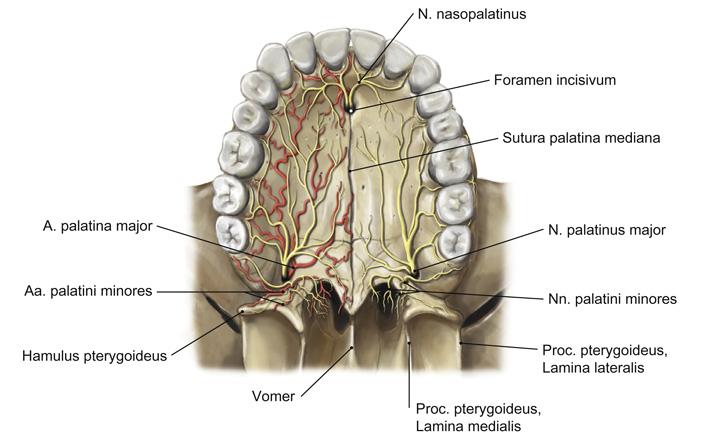

Fig 3.10c: a. maxillaris - sfenomaxillair deel - verhemelte

-

a palatina descendens

-

a palatina maior

aa palatinae minores

|

|